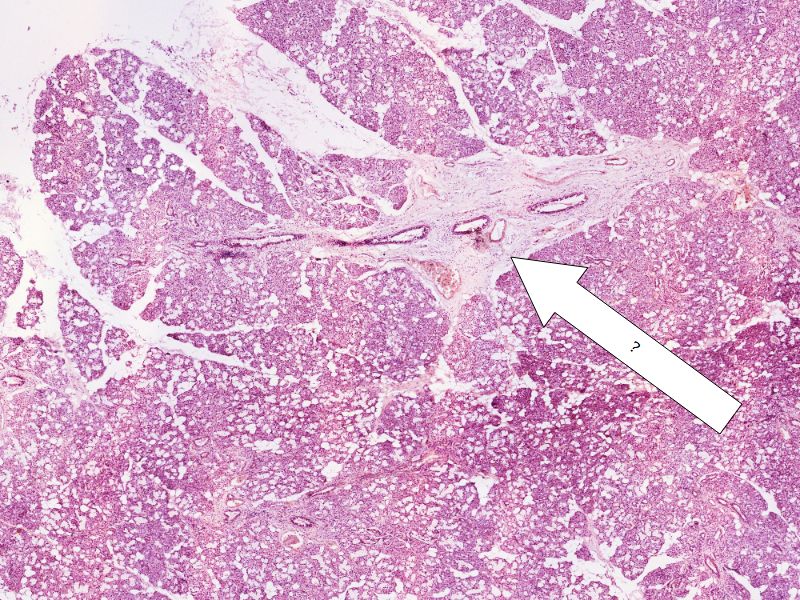

Fill in all the missing labels, and assess as you move through the slides. Answers on the down slide. It is important to do this using pen and paper, and not just glance through the images.